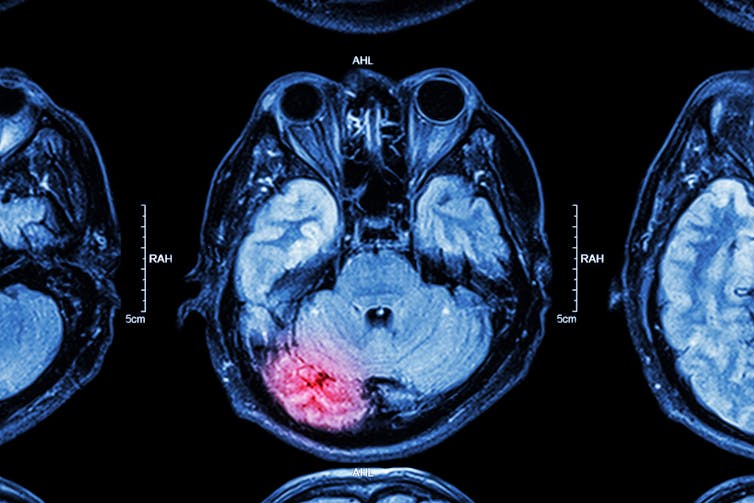

Lastly, we injected the thiol polymers into mice with traumatic brain injury. Brain scans showed that our polymer not only successfully concentrated in the damaged area of the brain but also provided immediate protection from further injury. Our thiol polymer was able to reduce reactive oxygen species in injured mice to just 3% over the normal levels found in uninjured mice. Untreated mice with traumatic brain injury had a 45% increase compared with uninjured mice.